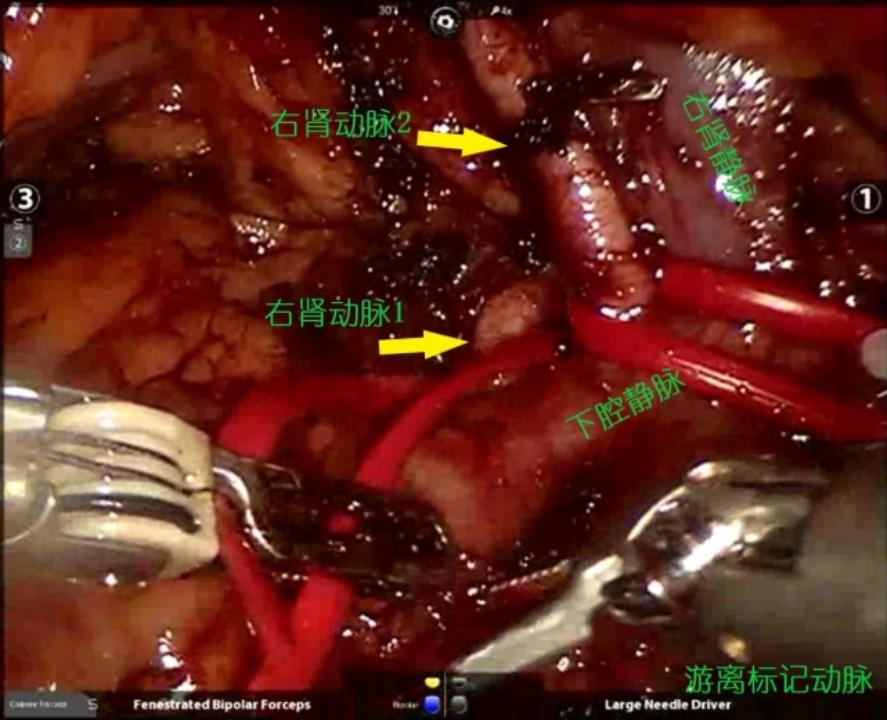

1.游离动脉:结合术前影像资料,有2支右肾动脉直接从腹主动脉发出,都是肾脏的主要血管,越过腔静脉后走形于右肾静脉偏下方的位置,因此我们在右肾静脉下方寻找到两支右肾动脉并分别予以游离标记。

3.切除肿瘤:阻断肾动脉后,选择肿瘤边界稍清晰的一边入手,切开粘连的肾周脂肪,显露肾实质及肿瘤边界,逐层切开寻及肿瘤包膜,沿包膜完整剥除肿瘤。

回顾本例手术,难点主要有两方面,一是肿瘤的位置比较刁钻,常规的经腰、经腹途径都很难暴露,需要对肾脏做充分的游离才能够显露出满意的操作空间。再加上患者肾周脂肪灶化严重,很难去确定明确的肿瘤边界,强行的游离只会造成肾包膜及肾实质的损伤。术中任善成主任也是在尝试游离后即刻停止,改选在肾动脉阻断后先行切开一点边界,寻及肿瘤包膜后沿包膜由点及面扩展切缘,从而在最小肾实质损伤下完整切除肿瘤。另外的难点是创面的缝合,创缘紧贴肾门上缘,底部血管密布,要在不损伤肾脏血供的前提下将创面充分缝合止血。任善成主任在操作创面内层的缝合上讲究精准缝合、精确止血,将创面的各种血管断端、集合系统创口仔细准确的缝合,既充分止血又保证肾脏血供不受影响,为保肾的成功奠定了基础。